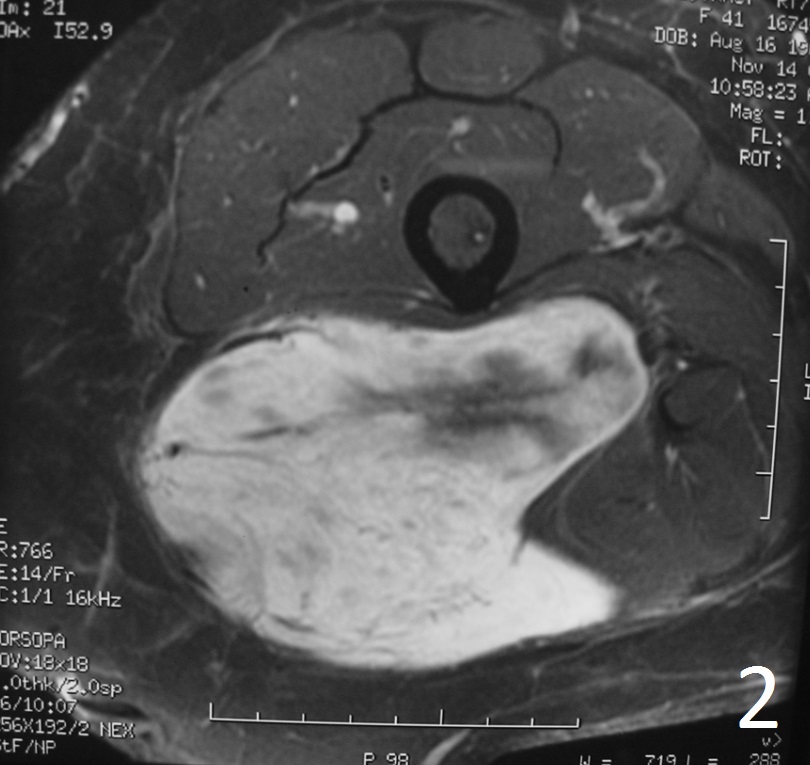

Radiographic imaging is used to help form a diagnosis. These include X-Ray, MRI, CT and Bone Scans

An example of an MRI is shown.